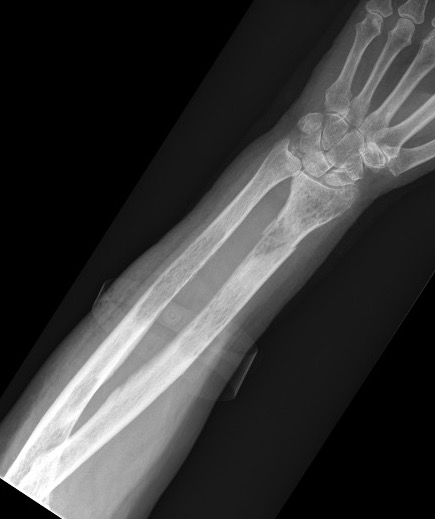

X-ray

1. Punched out lytic lesions

- axial and appendical skeleton

- widely disseminated

- soap bubble appearance

- no sclerotic reaction

2. Diffuse osteopenia

- in 15% to 25% of patients, no discrete lysis occurs

- diffuse osteopenia and osteoporosis are the only skeletal manifestations

4. Pathological Fracture